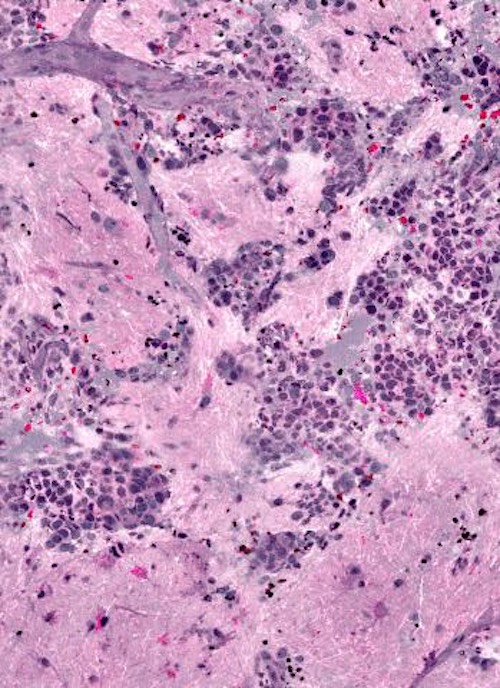

Tiled mosaic images built up from several individual SRH frames are comparable to the end results of conventional chemical staining. Credit: University of Michigan.